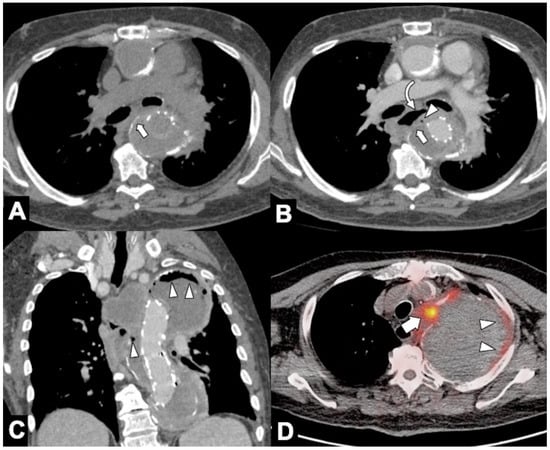

| Location | CTA Findings | Complete Rupture | Impending Rupture |

|---|---|---|---|

| Intramural | Increased aneurysm (>5.5 cm) | - | + |

| Rapid enlargement rate (>4 mm/year) | - | + | |

| Focal wall irregularity | + | + | |

| Hyperattenuating crescent sign | - | + | |

| Thrombus fissuration | - | + | |

| Draped Aorta sign | - | + | |

| Missing calcium sign | - | + | |

| Tangential calcium sign | - | + | |

| Luminal | Aortoesophageal fistula | + | - |

| Aortobronchial fistula | + | - | |

| Periaortic stranding | - | + | |

| Extraluminal | Contrast extravasation | + | - |

| Mediastinal hematoma | + | - | |

| Pleural hematoma | + | - | |

| Pericardial hematoma | + | ± |